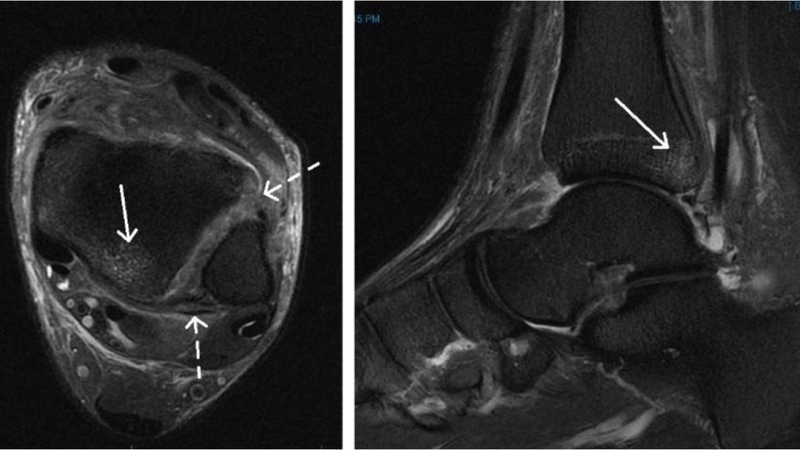

Để xác định chính xác loại chấn thương, cần thực hiện các phương pháp chẩn đoán hình ảnh. X-quang thường được sử dụng đầu tiên để phát hiện gãy xương, trong khi MRI có giá trị trong việc đánh giá mức độ tổn thương dây chằng trong các trường hợp nghi ngờ bong gân.

Nhận biết sớm các triệu chứng bong gân để xử lý hiệu quả 5

MRI có giá trị trong việc đánh giá mức độ tổn thương dây chằng trong các trường hợp nghi ngờ bong gân